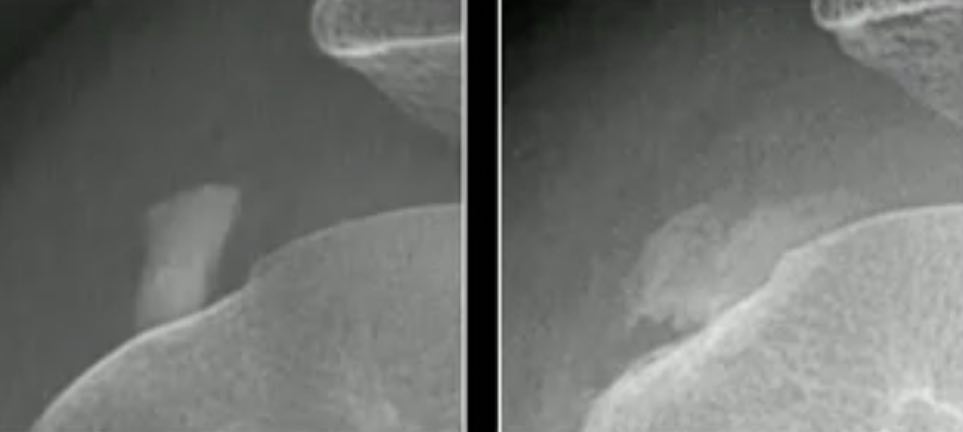

Résorption de PCB

Dépôts de cristaux de phosphate de calcium basique = épaule ++

- calcifications dans les tendons péri-articulaires denses, amorphes, bien limités

- résorption = ↘ densité et contours irréguliers

- ± érosion et migration intraosseuse